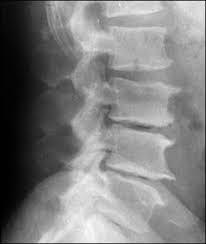

These are the kinds of x-rays we as chiropractors see every day. Pretty scary, huh? If you show these x-rays to a person in the medical field, they will say, "Oh, this person has osteoarthritis". Breaking down that label - osteo = bone, arth = joint, & itis = inflammation - your bone-joint is inflamed. But as chiropractors, we always ask, "Why?" Why did THAT joint degenerate but the one nearby - just as old as the other one - not have bone spurs?

Bone spurs or osteophytes, are bony projections that form off of the

bones of the spine, (vertebra) and joints of the extremities, (shoulders,

elbow, wrists, hip, knee, ankle and foot). They are the body's attempt to "shore up" an area of increased biomechanical stress by laying down more calcium.